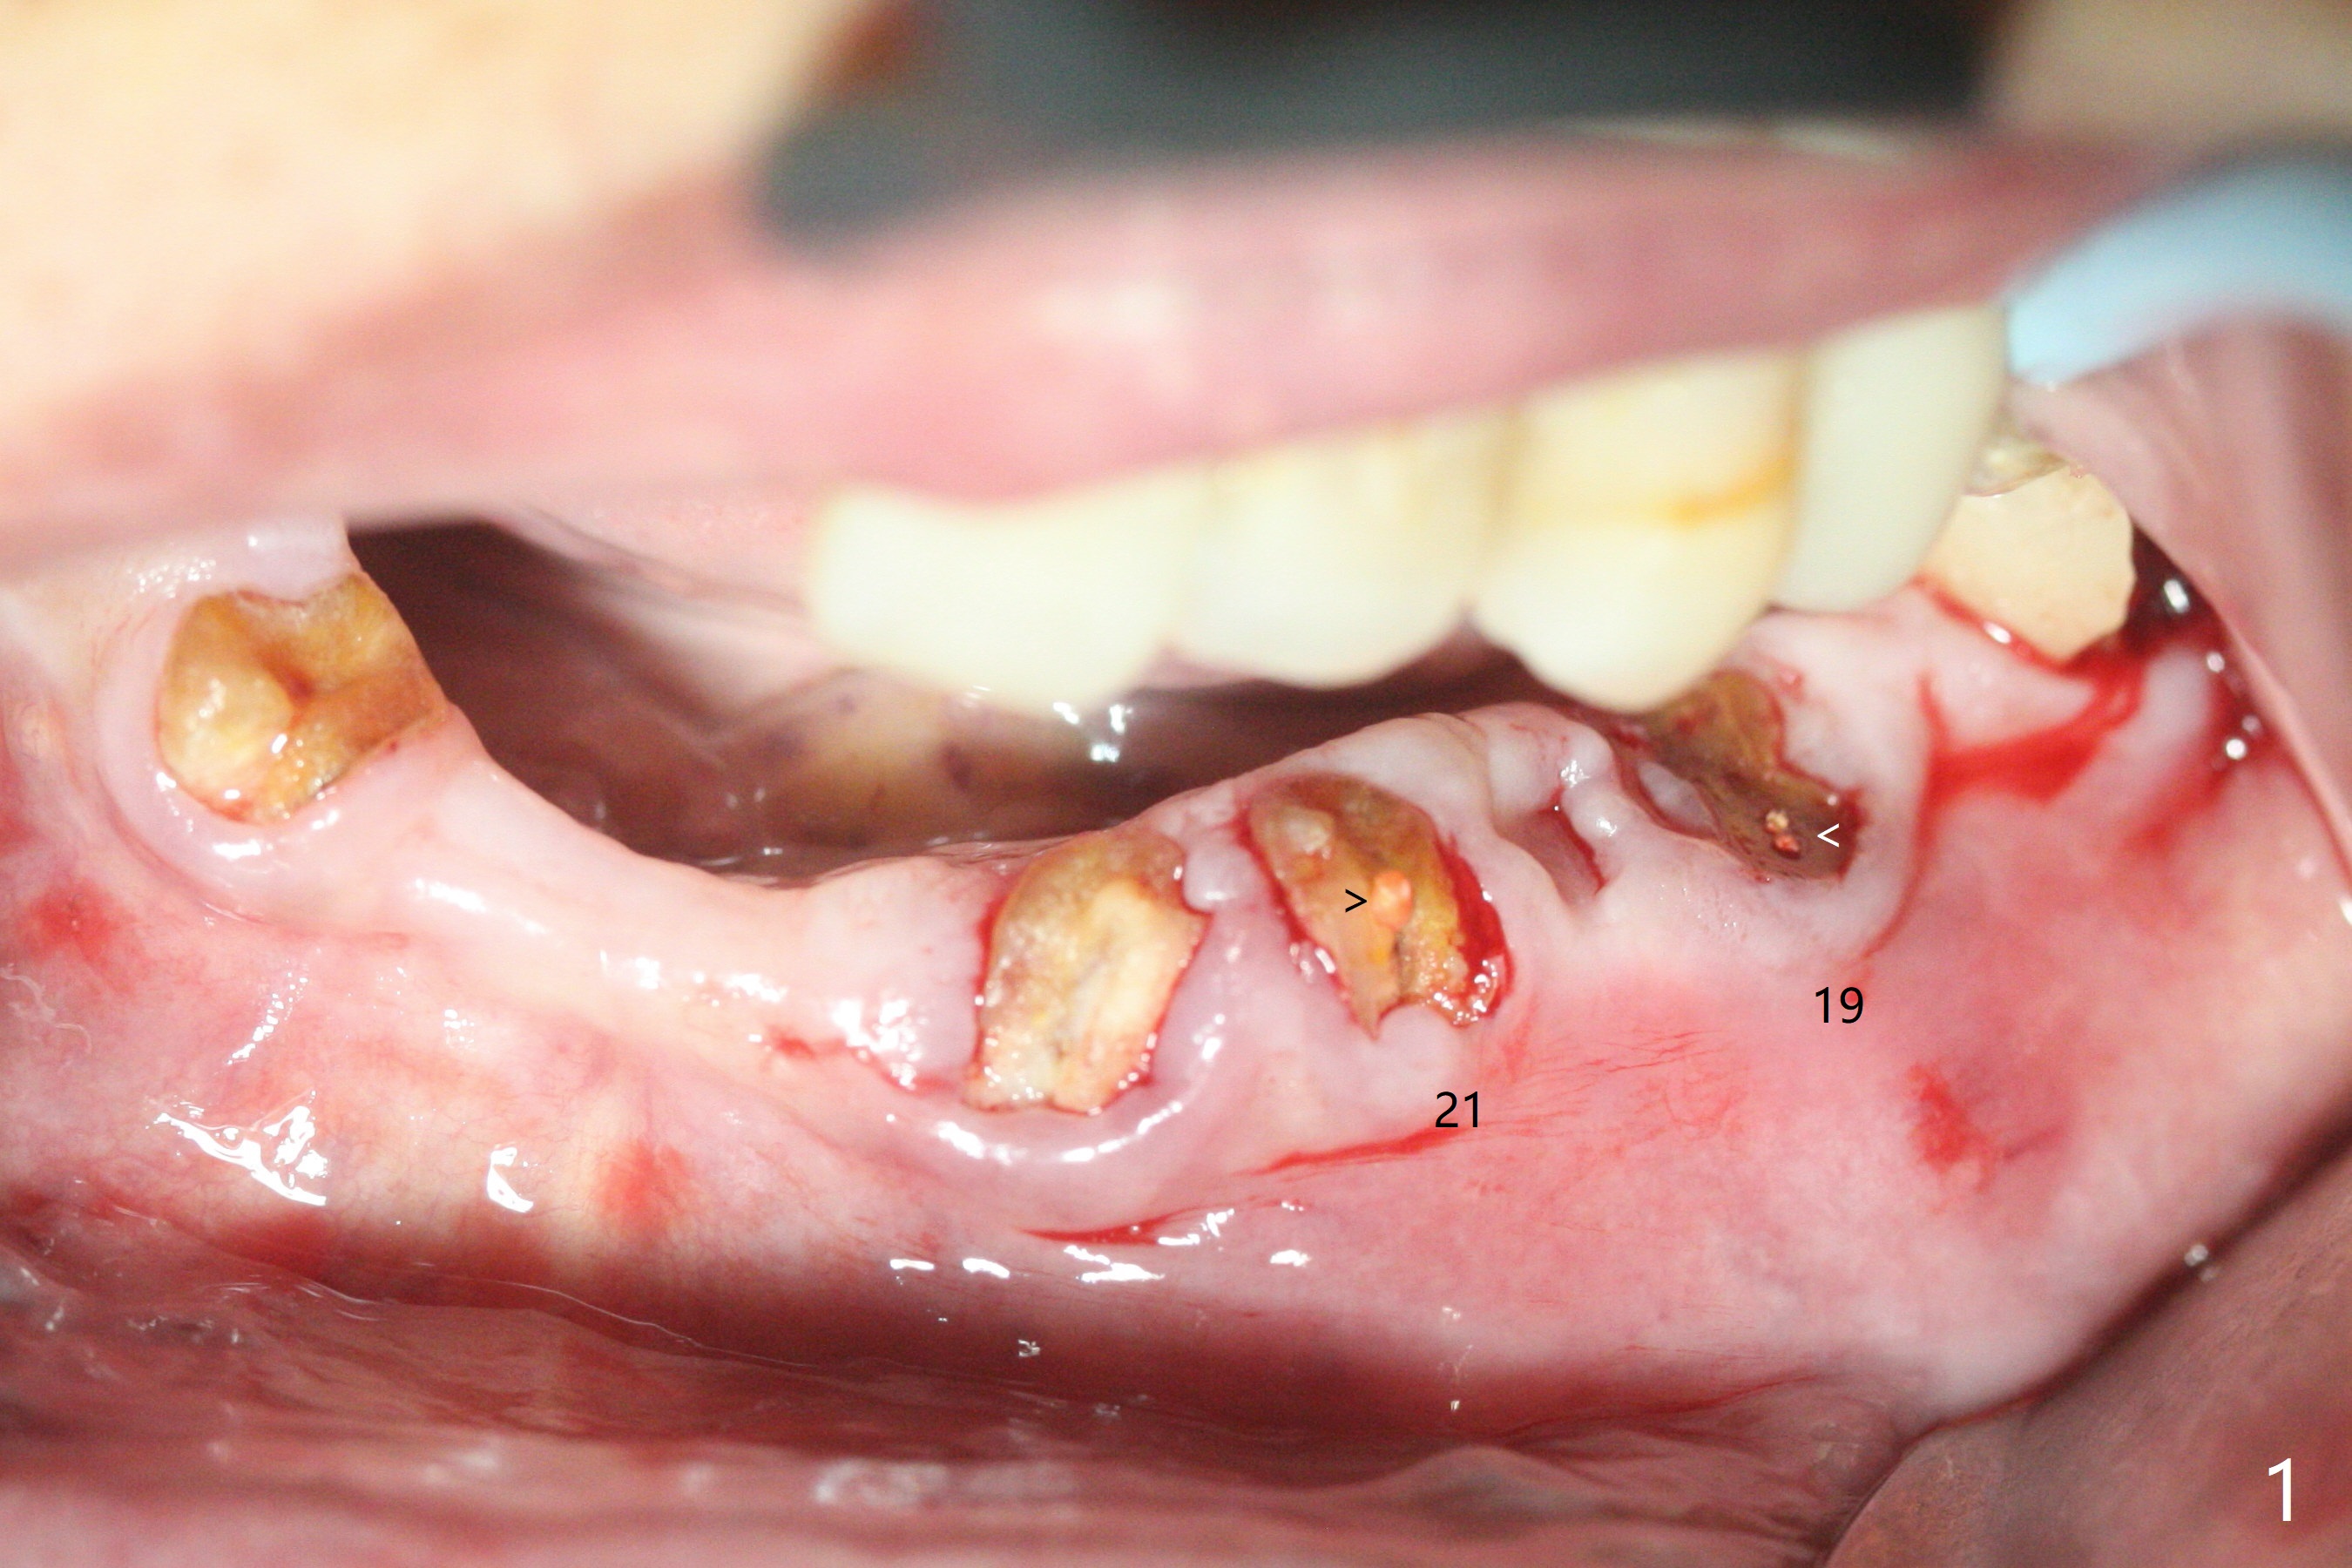

85岁女回诊所做27,28,30植牙,由于导板设计,所有7个残根需要拔除(图一,三),做过根管治疗牙齿(图一:箭头),如19,21号牙,颊侧骨板吸收比没做过的轻(图二,四:箭头(根尖穿孔))。30号牙根尖吸收多,使用短小植体(图五),根尖骨质少,初步稳定性差,不能即刻修复(图六),是这次手术最大欠缺的部分。原来准备在30号牙位做临时牙冠,局部托牙卡环恢复作用,还好27,28植体(图八)稳定性好,连体临时牙冠帮助托牙固定。27,28植体不足之处是放置太深,基台与牙槽骨(图八:*)接触,可能造成骨质吸收。其实27号植体(3.5x9mm)植入后必须去除,与基台连接后,一起徒手植入,所以深度控制不好。术后一个月10天病人回来做20和22号牙种植(拔牙后一,两个月),由于角化龈窄,切开导板植入,好处容易判断22号牙植体深度,植深后,两个植体周围放置骨粉(图九,十),然后胎盘膜(两个8x8毫米),4-0 PGA缝线。